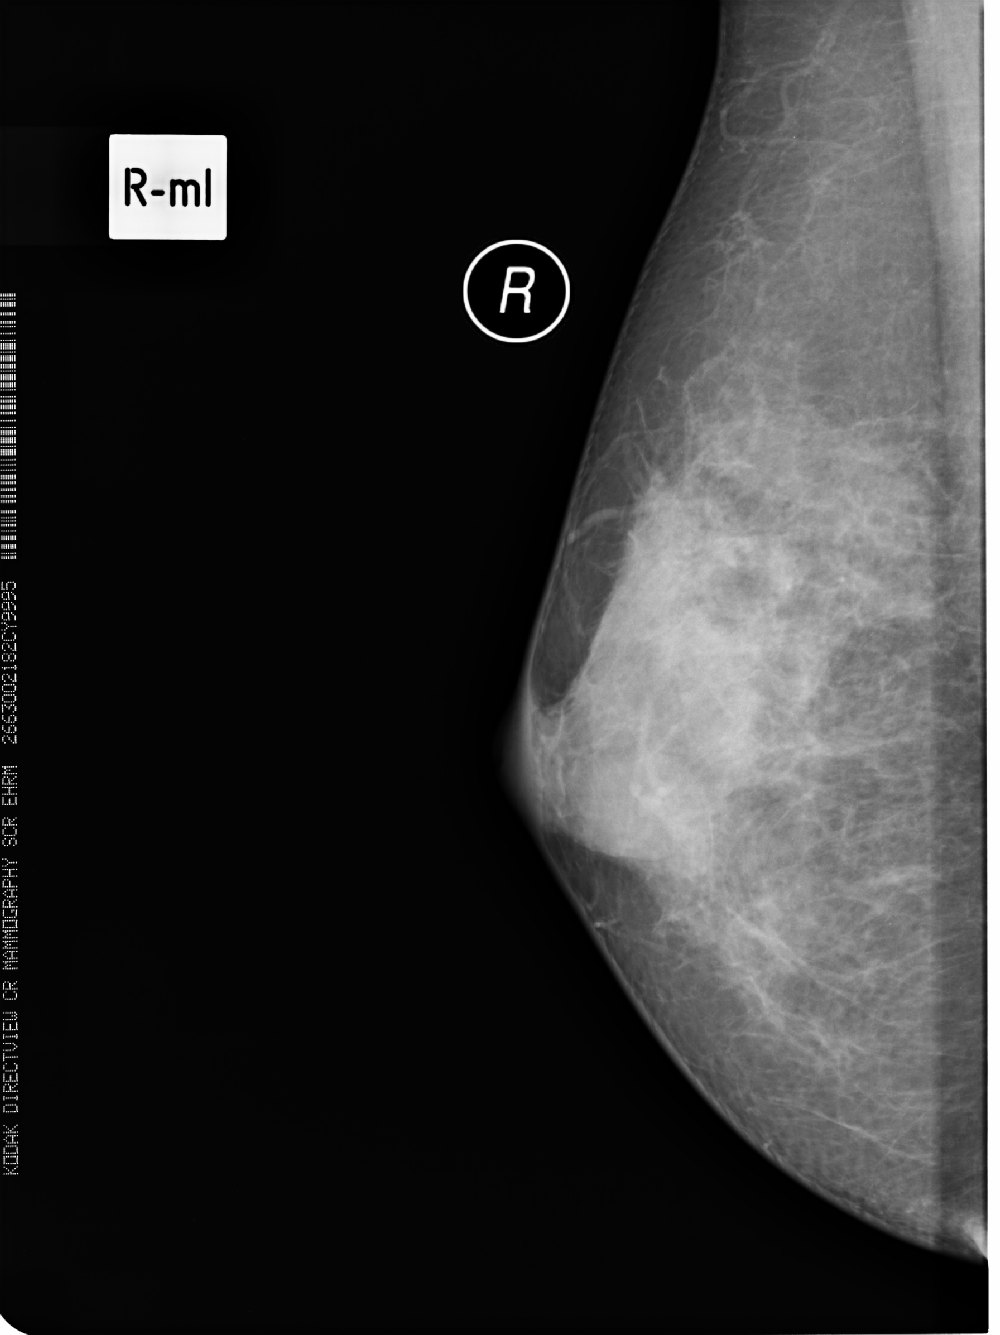

标题: X6857:女,39岁,右乳肿块半年余;三天后公布结果。 [打印本页]

标题: X6857:女,39岁,右乳肿块半年余;三天后公布结果。

左侧乳腺局部不对称性密度增高,局部可见纠集征象,左侧乳腺癌不除外。

所见乳腺内见斑片状高密度影,未见明显占位征象,考虑乳腺小叶增生,结合临床及b超。

右乳腺瘤可能

x6857,女,39岁,右乳肿块半年余;病理结果。

“右”乳纤维腺瘤

纤维腺瘤诊断要点:1,40y以下青年女性2,类圆形肿块,边光、锐利,可有分叶,密度或信号均匀,部分可见粗颗粒样钙化3,增强多呈缓慢渐近性直均匀强化或离心样强化。